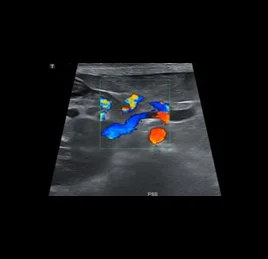

• 혈관 이상 - PSS

• 동맥관 개존증 - PDA

장기의 구조뿐 아니라 혈류, 운동성, 기능 변화까지 평가할 수 있어, 다양한 질환의 조기 발견과 모니터링에 효과적입니다.